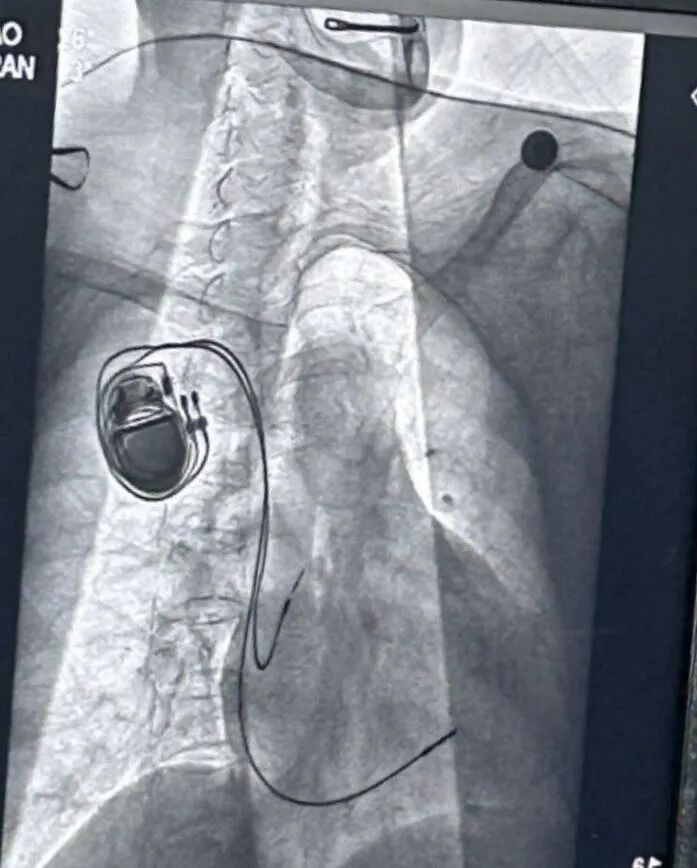

当日,患者在我院迅速完善了各项检查,动态心电图提示:窦性心动过缓,窦性停搏(3.87秒),交界性异博,二度II型房室传导阻滞,最大心率62次/分,最小心率27次/分。经过专家会诊,张大爷被确诊为病态窦房结综合征,这是一种因窦房结功能异常导致的心律失常疾病。根据患者病情,为防止猝死等严重后果的发生,医院决定为他实施永久起搏器植入术。

7月16日晨,历时40分钟左右,张大爷接受永久性起搏器植入术毕安返病房。术后恢复良好。7月17日,张大爷顺利出院。这次紧张迅速又成功的治疗经历,不仅让张大爷重获了“心”动力,也让他对社区医院三级联动机制赞不绝口。